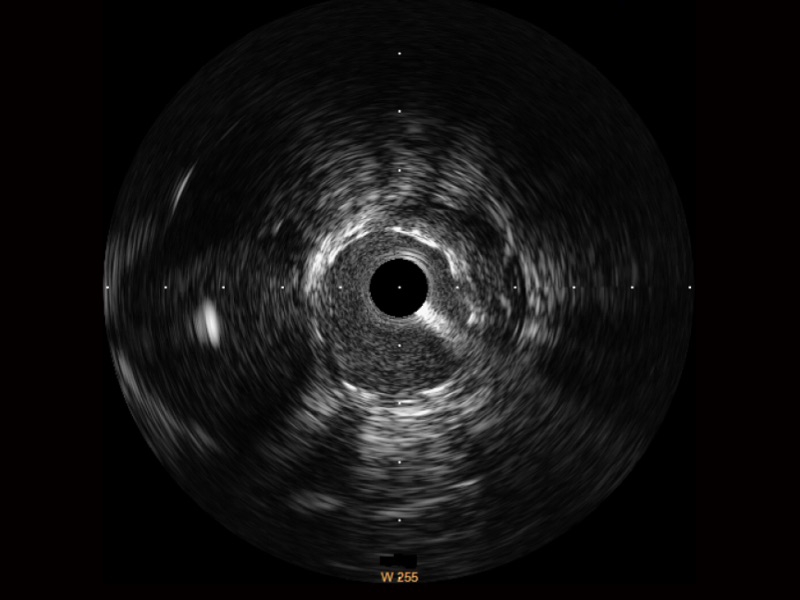

开立宽频IVUS图像

传统IVUS图像

对比传统IVUS导管成像,开立宽频IVUS图像的近场支架梁显影更细腻,远场中膜外血管仍清晰可辨,兼顾远中近,兼顾分辨力与穿透深度